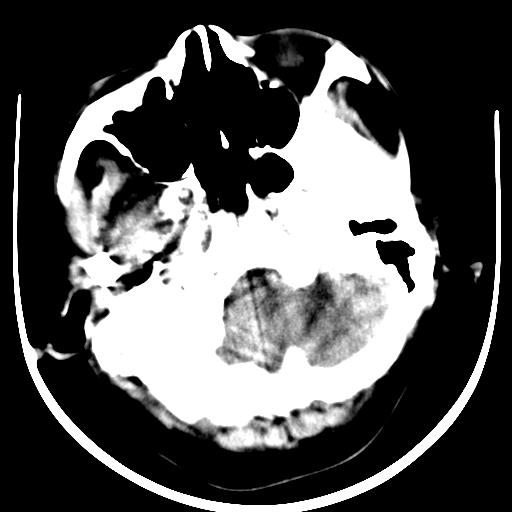

标题: CT16838:男58岁,意识不清2小时,请会诊出血部位该如何写。 [打印本页]

标题: CT16838:男58岁,意识不清2小时,请会诊出血部位该如何写。

1)脑干、左侧桥小脑臂及小脑蚓部出血破入蛛网膜下腔。2)左侧基底节区灶性出血,不排除钙化灶。3)脑室系统少量积血。4)脑积水。

(患者病情危重,出现不自主运动——是引起图像质量不佳的主要原因)